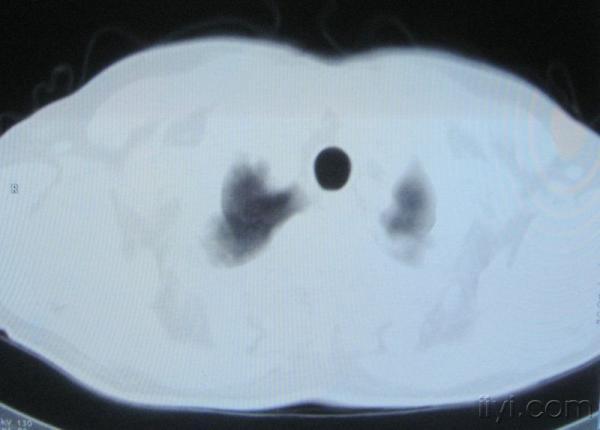

男。60岁,胸片示支气管炎治疗后复查CT。

根据位置考虑应该是淋巴结,密度不均,是因为肿大的淋巴结中心液化坏死

你指那个肯定是淋巴结,中央系坏死,这很常见,特别在双侧腹股沟会经常看到。这个双侧腋窝及纵隔见多发小淋巴结征。

应该是淋巴结没问题的,中心液化坏死是有这种情况的~~胸科常见到